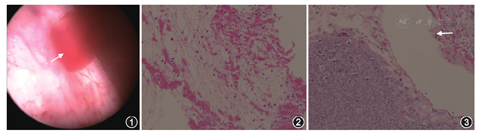

患者 男性,56岁。因"肉眼血尿1 d"于2015年1月5日入院。患者1 d前无明显诱因出现全程肉眼血尿,有小血块及血条排出,无尿频、尿急、尿痛,无腰、腹部疼痛,无发热,大便如常。既往无特殊病史。体检:体温36.6 ℃,心率70次/min,呼吸20次/min,血压135/80 mmHg(1 mmHg=0.133 kPa)。腹部及泌尿系统专科检查未见异常。实验室检查:尿潜血(+++),尿白细胞(-),尿蛋白(+)。泌尿系统超声及CT增强扫描结果显示双侧肾脏及膀胱未见异常。尿液脱落细胞学检查未见肿瘤细胞。入院后第2天行膀胱镜检查,膀胱内无新生物,右侧输尿管间歇性喷射血性尿(图1),输尿管硬镜检查未发现右输尿管内新生物,输尿管软镜见肾盂内突起肿物,广基底,界清,表面光滑并可见条状结构,局部活动性出血。肾盂肿物取活检,病理结果显示:肾盂内纤维素样组织(图2)。因不能除外恶性病变可能,与患者及家属沟通后行腹腔镜下右肾、右输尿管全长、膀胱袖状切除,术后病理结果显示:右肾盂海绵状血管瘤(图3)。